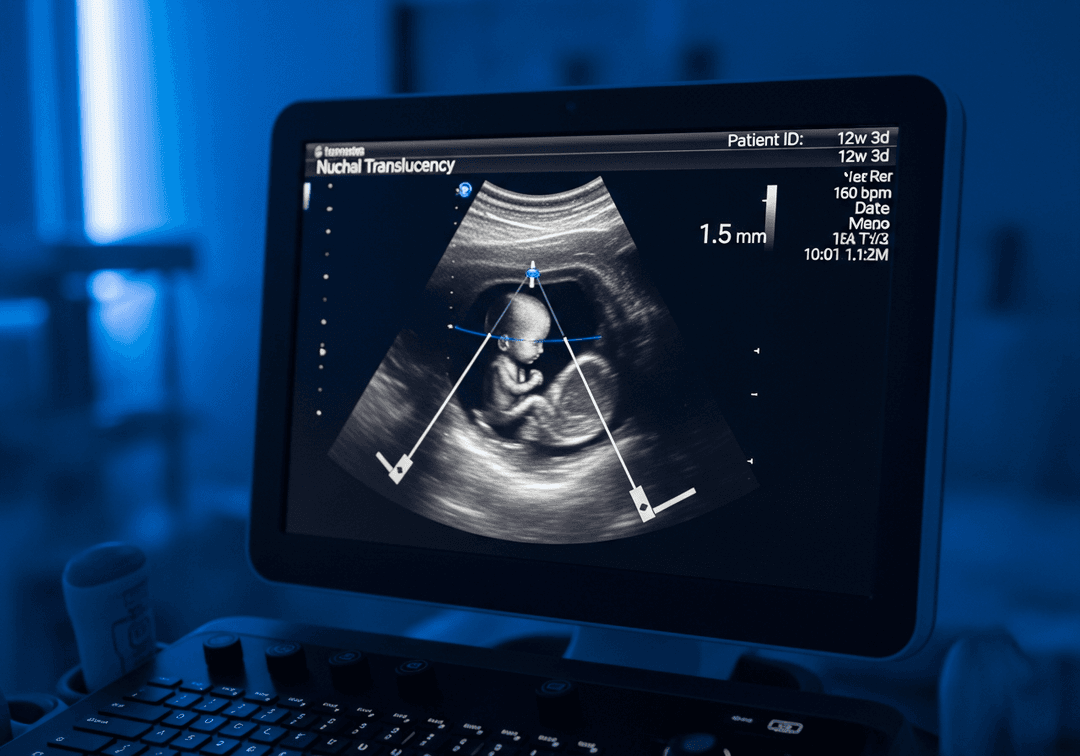

La mesure doit être réalisée entre 11 SA et 13 SA + 6 jours, lorsque le fœtus mesure entre 45 et 84 mm (longueur cranio-caudale). L'échographiste, agréé par un réseau de périnatalité, positionne les curseurs précisément sur les bords de l'espace nucal selon les critères du CFEF.

La clarté nucale est interprétée en fonction de la taille du fœtus (LCC), selon des courbes de percentiles. Il n'existe pas de seuil fixe 'normal' : c'est le risque combiné (clarté nucale + marqueurs sériques + âge) qui détermine la conduite à tenir.